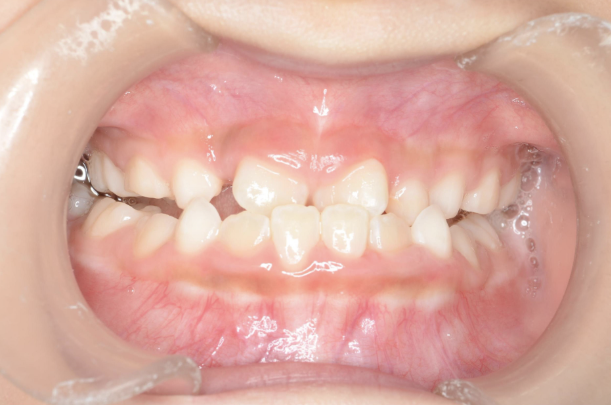

お子さんが「矯正治療」をはじめる時に直面する問題は 「装置が目立つ」、 そして「歯を抜く」ことがあげられます。

10歳を超えてからの治療開始ではそのようにならざるを得ないことが多いのです。

しかしながら、5〜7歳頃に治療をスタートすれば 目立ちにくい装置で、歯を抜かずに治療できることがあります。

10歳を過ぎてからの矯正治療の場合、大人の歯を抜いて治療することが多くなります。 一方、下の前歯が生えてくる5〜7歳頃から治療を始めると、大人の歯を抜かずに治療することが可能です。 抜かずに治療するには早期に治療を開始することが大切です。

歯並びが悪いのは、あごの骨が成長不足で小さいことで起こります。 当院で行なっているこどもの歯ならび治療はあごの骨に働きかけることができます。 骨に働きかけることで成長不足のお子さんの骨が成長して、顔つきが良い方向に変わっていく可能性があります。 実は大きくなってからの矯正治療は歯が並んでいるだけで骨やお顔つきは変わっていないのです。 5〜7歳ぐらいで治療を開始すると成長不足の骨に働きかけて、より良い顔つきになれる可能性があります。